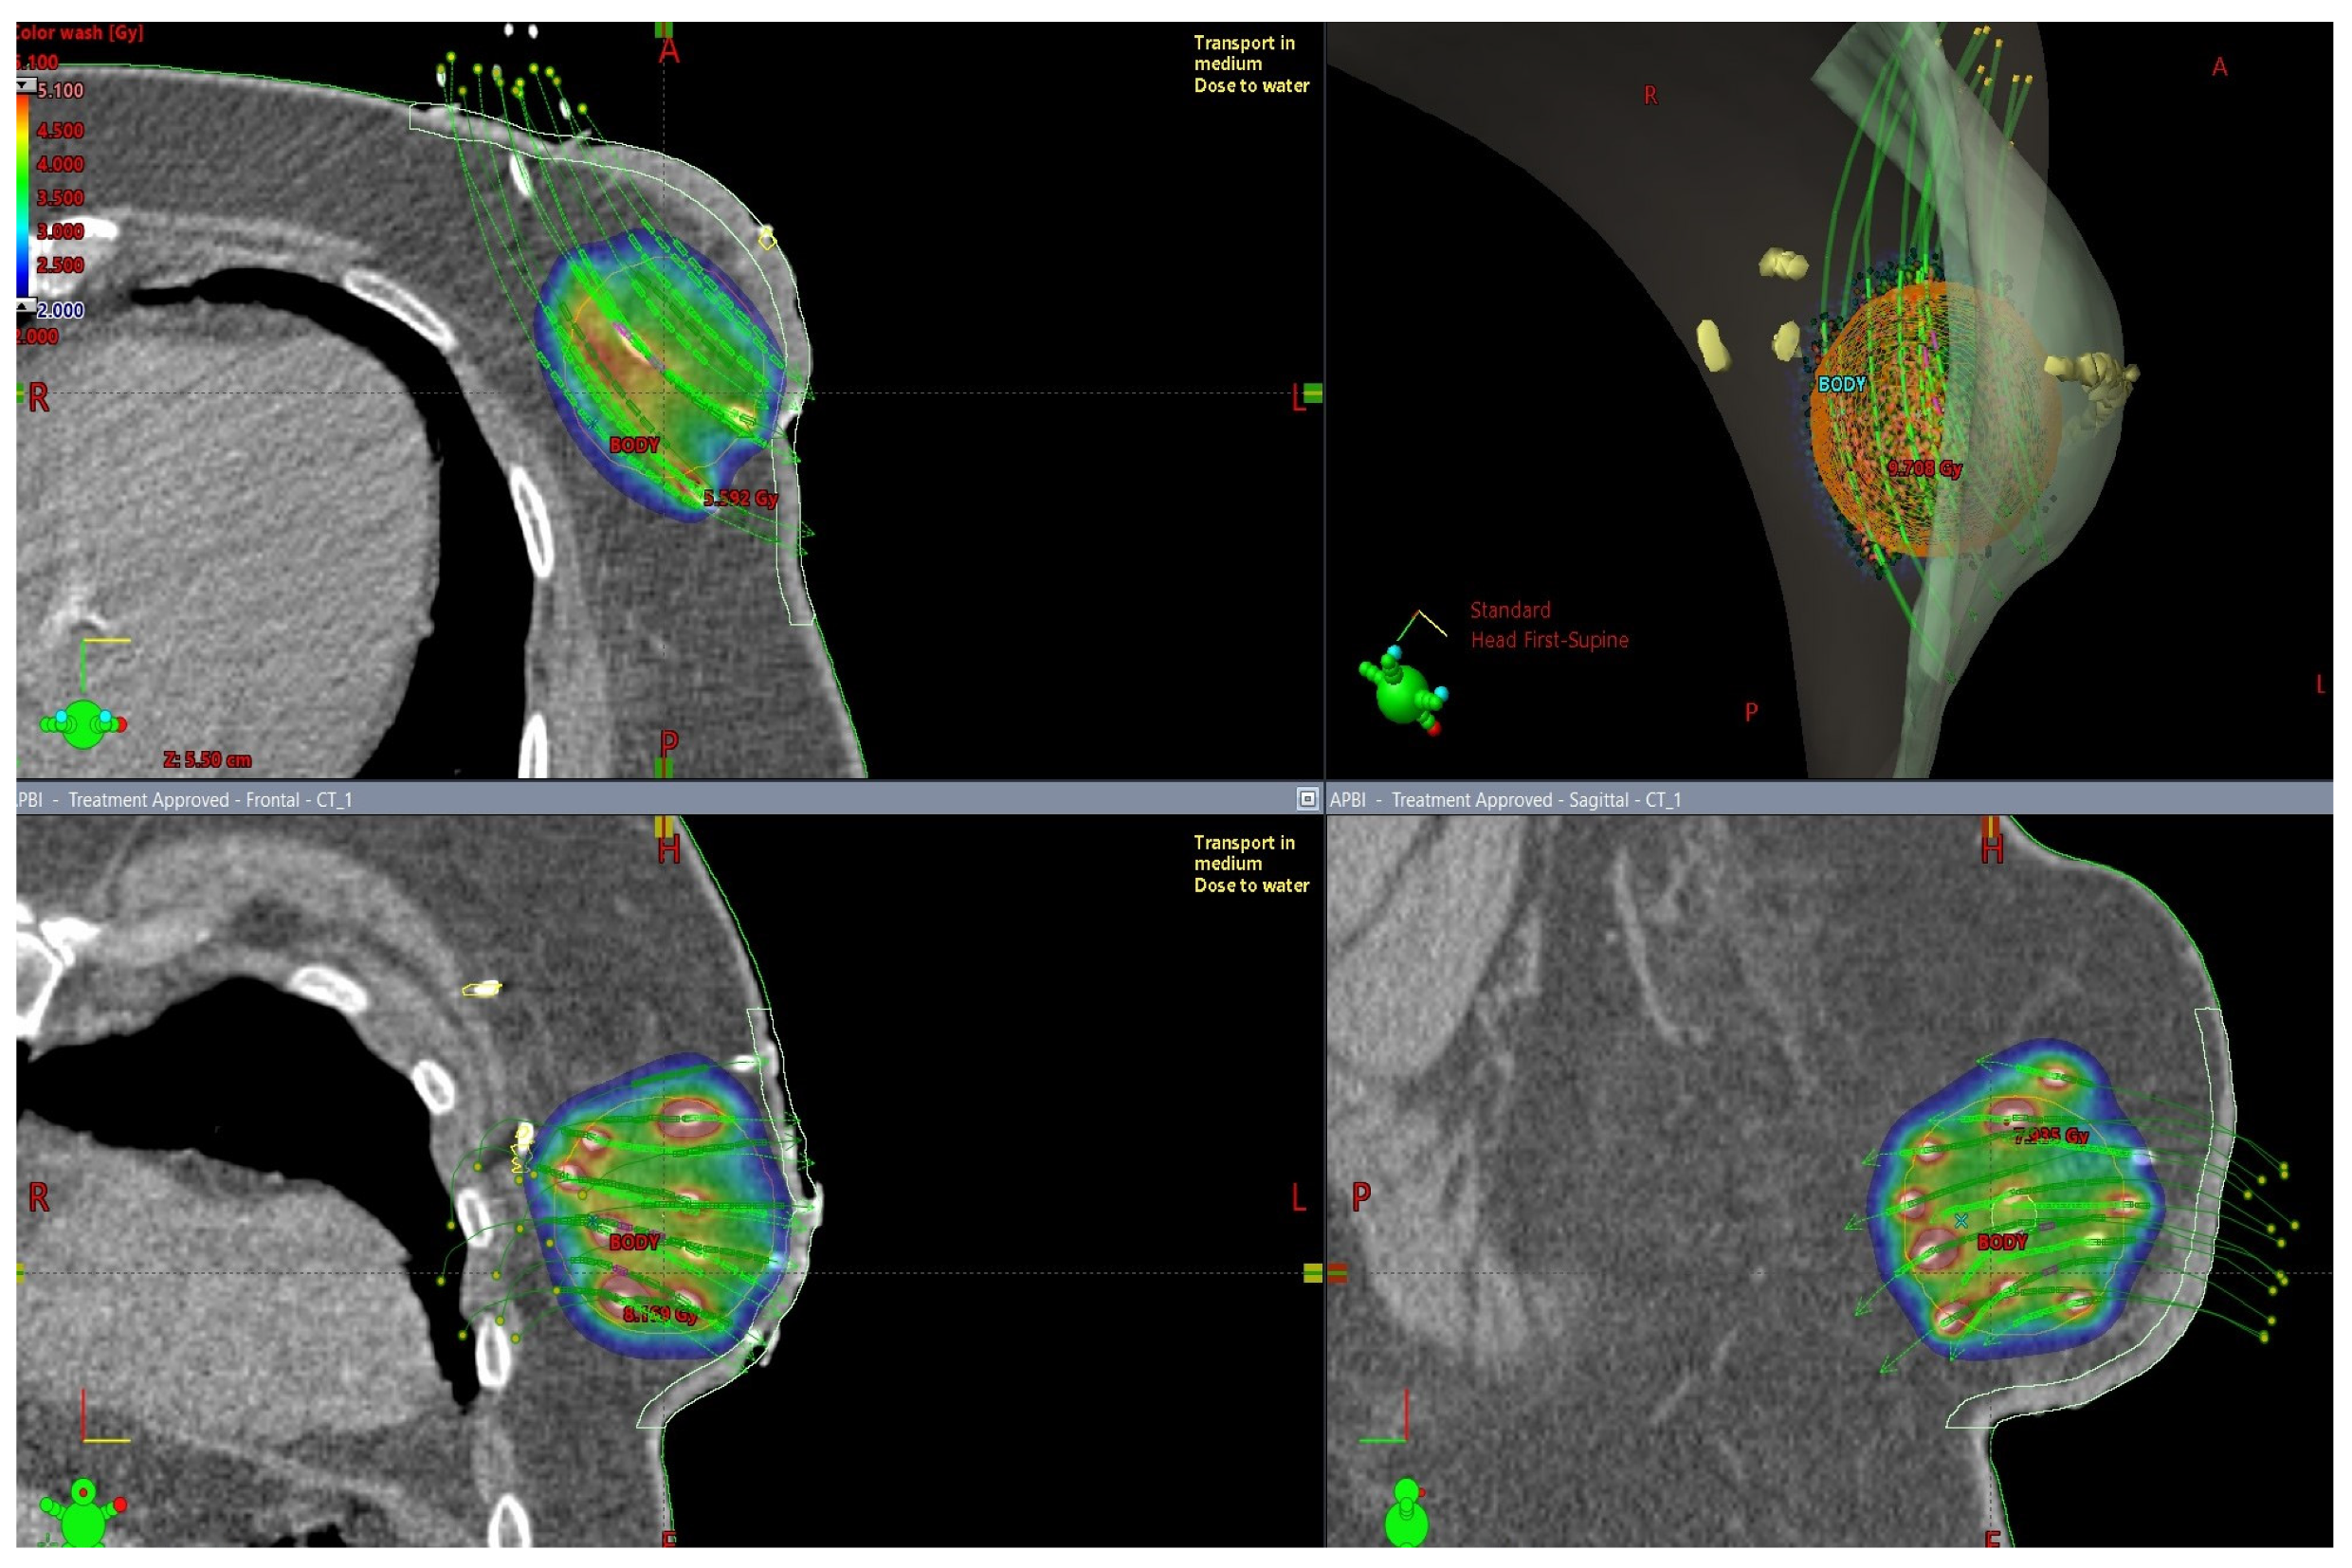

Figure 1.

3D visualization of multicathether interstitial APBI technique from different viewing angles, delineation and dose calculation: interstitial catheters—white, CTV—orange, skin—light green, surgical clips and skin incision—yellow. Dose 3.4 Gy per fraction. Dose distribution presented by the color distribution: V150 (5.1 Gy)—red, V100 (3.4 Gy)—green, 2 Gy—blue.